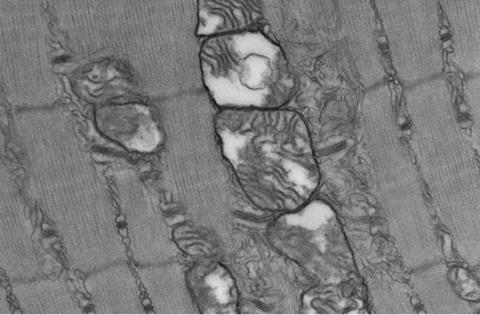

Undoubtedly, the discoveries emerged when the researchers explored mice with the gene encoding the Musashi-2 protein deliberately "knocked out." These Msi2-deficient mice presented with calf muscles characterised by a substantial reduction in mass, a pallid appearance, and diminished strength. As the team peered through the lens of a microscope, the root of this muscular decline became apparent: a marked reduction in the population of type 2a fibres, a variety of "fast" fibres distinguished by their unique blend of endurance reminiscent of "slow" fibres. Additionally, the Msi2 knockout mice demonstrated a compromised ability to metabolise sugars, mirroring the metabolic dysregulation observed in diabetes. The culprits behind this metabolic impairment were fewer myoglobin and mitochondria, both indispensable to produce cellular energy. Remarkably, the researchers found that this affliction could be rectified by reintroducing Msi2 specifically into "fast" fibres, thereby restoring the levels of myoglobin and crucial protein markers associated with mitochondrial function. This observation underscored Msi2's role in governing proteins associated with sugar metabolism while wielding influence over the composition of different fibre types within the tapestry of skeletal muscle tissue.